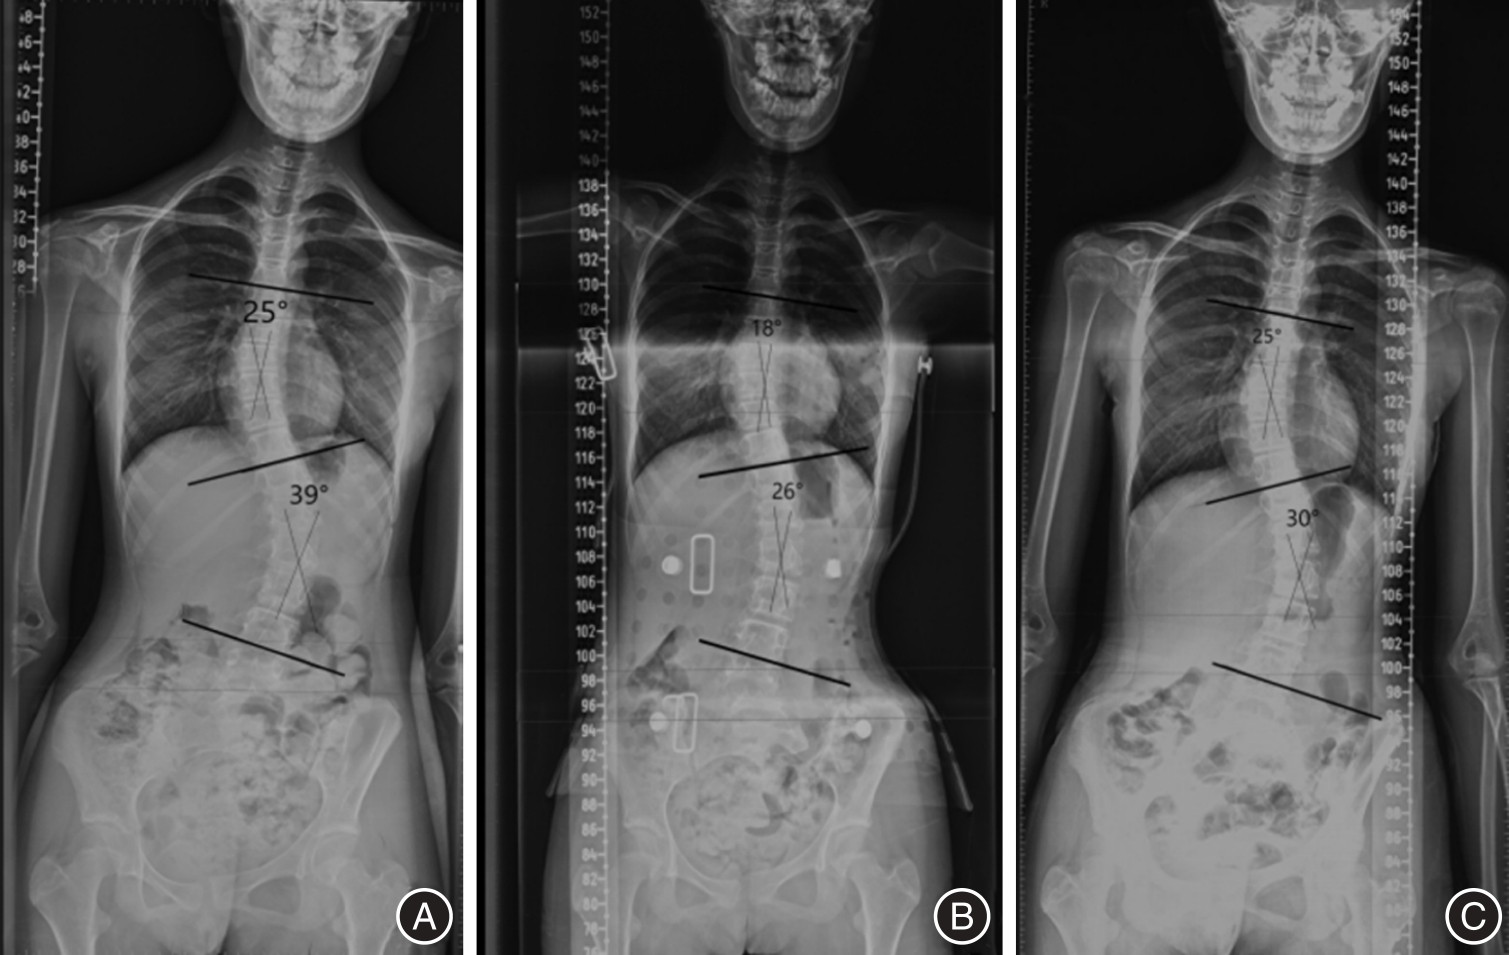

Objective To evaluate the efficacy of Schroth PSSE combined with 3D printing braces in the treatment of adolescent idiopathic scoliosis. Method Forty patients were included and divided into a support group (3D printing support group) and a support + exercise therapy group (3D printing support + Schroth PSSE group). Excluding outliers and lost follow-up data, 32 patients were ultimately included, with 16 patients in each group. Wearing time ≥ 18 h for both groups of 3D printing supports. The intervention period of Schroth PSSE is 12 weeks, and exercise is maintained after 12 weeks until the end of follow-up. The longest follow-up time for the brace group was 25 months, with an average follow-up time of (15.00 ± 1.29) months. The longest follow-up time for the brace+exercise therapy group was 24 months, with an average follow-up time of (16.59 ± 1.01) months. Relevant indicators were evaluated after follow-up. Results The support and exercise therapy group showed better improvement in Cobb angle and trunk rotation angle (ATR) than the support group, with statistically significant differences (P < 0.05); The distance between the midpoint of the C7 vertebral body and the midline of the sacrum (C7-CSVL) in the support and exercise therapy group showed a statistically significant difference before and after treatment (P < 0.05), while there was a significant difference before and after Apical Vertebral Translation(AVT )treatment (P < 0.01). There was no statistically significant difference compared to the support group (P < 0.05); In terms of SRS-22 score, the brace + exercise therapy group can comprehensively improve the SRS-22 score. Conclusion The combination of Schroth PSSE and 3D printing braces has a better effect on improving Cobb angle and torso rotation angle, improving coronary imbalance, increasing patient satisfaction, and improving quality of life compared to using 3D printing braces alone.